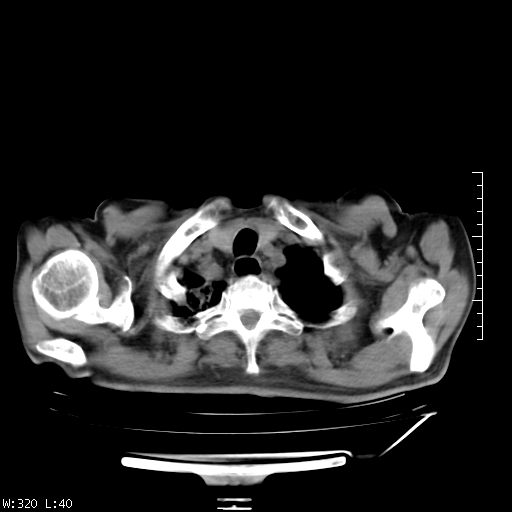

标题: CT23994:男、72、咳嗽、气短两月余,近来消瘦。 [打印本页]

标题: CT23994:男、72、咳嗽、气短两月余,近来消瘦。

右上肺实变,与胸膜关系密切,右肺容积缩小,隆突下淋巴结增大,考虑1 肺结核 2 肺癌

右上肺大片状密度增高影,与胸膜关系密切,内见低密度透亮影,胸膜下可见三角形不张影,左下肺沿支气管走形结节影,纵膈内淋巴结显示。考虑结核并疤痕性不张可能性大,建议穿刺活检,排除肺泡癌。